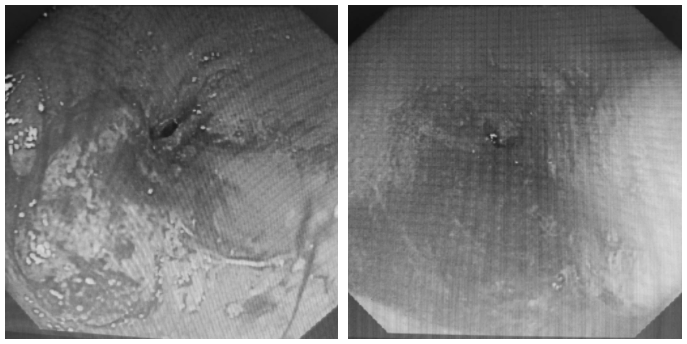

如罗晓华护士长之前判断一样,老人为食管恶性肿瘤占位,食道肿物基本已经环周,只留下了一个非常细小的管腔,正常胃镜根本无法通过,并且肿物稍微触碰摩擦就出现渗血出血的情况,并且老人身体衰弱,难度和风险很大。

由于老人家属明确不考虑住院治疗,仅希望完成置入胃管,王业忠副主任医师改变策略,选择更换鼻内镜下镜,尽可能减少对老人食管的损伤。最终在导丝引导下成功置入。